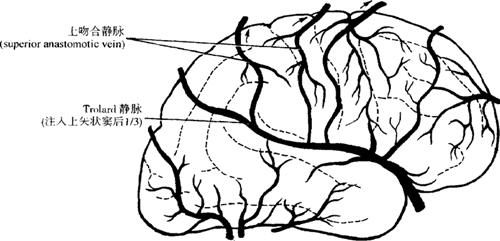

1.脑浅静脉 大脑浅静脉的形态学特点是:①个体差异大,几乎每个人部不相同,甚至同一个体左右两侧也不尽相同;②浅静脉面有较多的吻合;③浅静脉的数量远比动脉要多,管径也比动脉粗。大脑表面的静脉主要有(图12-87):

图12-87 脑的浅静脉

(4)上大静脉吻合(superior magna anastomotic vein)是大脑中静脉连接上矢状窦的静脉,由于Trolard(1870)首先发现并加以记录,故也称Trolard静脉。它是指沿大脑外侧沟走向后上方,最后流入上矢状窦后1/3者。除此之外,存在于半球背外侧面的所有大脑上、中静脉间的吻合均称为Trolard吻合。据观察Trolard吻合(8%)多见于Trolard静脉(13.1%)(图12-88)。

图12-88 上大吻合静脉(Trolard吻合)